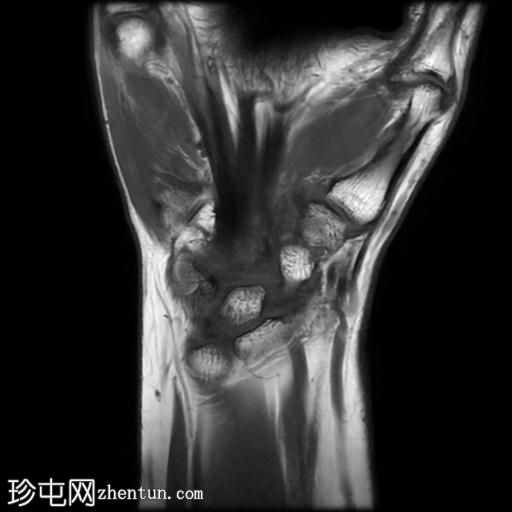

冠状位

T1加权像

桡侧腕屈肌腱鞘内可见液体信号,提示腱鞘炎

手部桡侧腕屈肌腱远端扁平,邻近的大多角骨嵴和舟骨结节可见反应性骨髓水肿

MRI结果提示存在桡侧腕屈肌腱病变,以及大多角骨和舟骨结节骨髓水肿。桡侧腕屈肌(FCR)肌腱病通常表现为腕关节掌侧(靠近桡侧)疼痛。这种情况通常是由于长期过度使用造成的,尤其是在肌腱与粗糙表面接触的部位。